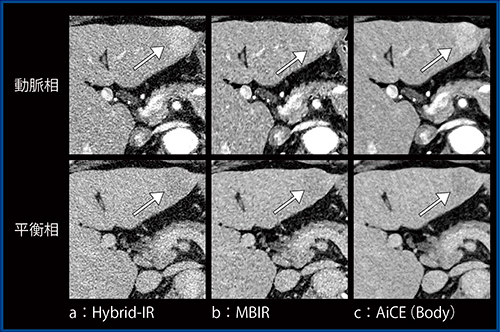

超高精細CTは高分解能であることが大きな利点であるため,HCCの形態診断に利用できると期待した。原発性HCC症例(70歳代,男性:図1)について,Hybrid-IR(a),MBIR(b),AiCE(Body)(c)で再構成した画像を比較すると,AiCE(Body)では非常に良好なノイズ低減が得られているものの,腫瘍の境界(→)については若干不明瞭になり,視認性の改善があるとは言い難い画像であった。

図1 Hybrid-IR,MBIR,AiCE(Body)の比較